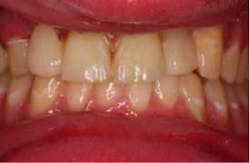

The patient was treatment planned alongside the periodontist to remove the No. 7 implant and graft the bone lesion. A cover screw was planned to be placed on the No. 10 implant and bury it under the soft tissue for esthetics. Two ceramic (e.max) Maryland bridges were placed to restore the missing laterals, bonding to both adjacent teeth. The possible complications were explained to the patient, and he consented to treatment. Initial data was gathered including photo grafts, mounted cast, and a diagnostic wax-up. The restorative plan was to be completed using a Planmeca E4D scanner and mill to fabricate the restorations.

Three days before he left, the patient presented for treatment, the No. 7 implant had been removed, and the site had been grafted, along with No. 10 implant being submerged. A modified lingual veneer preparation was made on the adjacent teeth. The lingual prep served two purposes, the first to increase surface area for bonding and the second to increase the connector cross-sectional area. The ideal cross-sectional area is 16 mm² (*).

The preps were scanned, along with a bite registration, opposing dentition, and the diagnostic wax-up for cloning. The restorations were designed and milled from monolithic e.max HT blocks. The restorations were stained, glazed, and crystalized to final shade and luster.

The restorations were etched with phosphoric acid, cleaned with Ivoclean (*), and bonded with universal bond (*). The preparations were isolated (isolation was very difficult in the area of No. 7 due to surgery the day before), etched, bonded, and the restorations were cemented. Special attention was paid to the occlusion on the FPDs, and all occlusal contact was removed from the connector area. Also, all anterior guidance was removed from the FPDs. The opposing dentition was reshaped to gain as ideal of a contact on the restorations as possible. The patient returned one prior to his leaving to verify his occlusion and post-treatment photographs. At this time, the patient was instructed about hygiene for the restoration and how to carefully function with the restorations. He seemed to be pleased with the functionality and esthetics of the restorations.